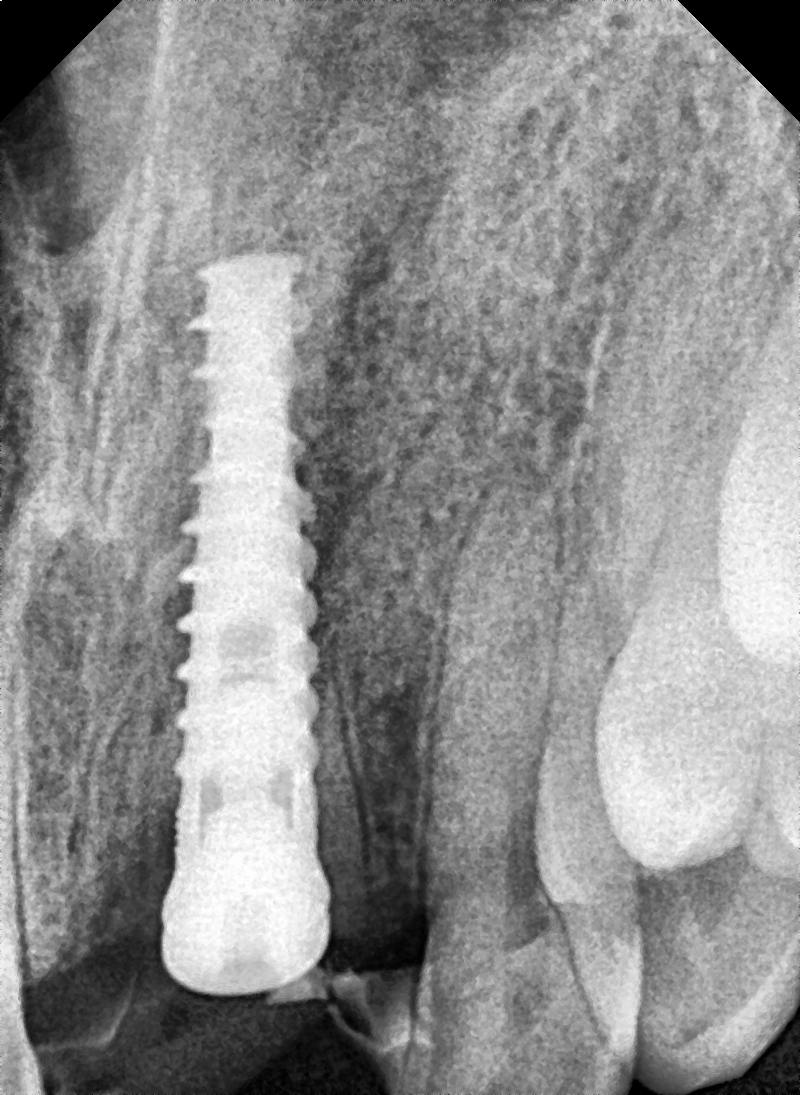

Images Of Dental Treatment Servcies Done At Our Hospital